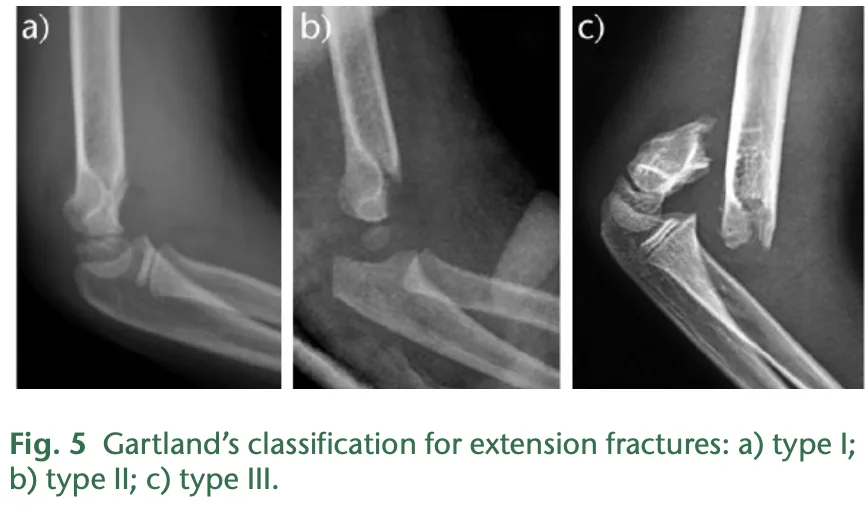

a) 転位がないtype I, b) 軽度の転位があるtype II, c) 完全に転位したtype III.

X線写真とCTを見たところ, Gartland分類type IIIで, 完全に転位した状態でした.